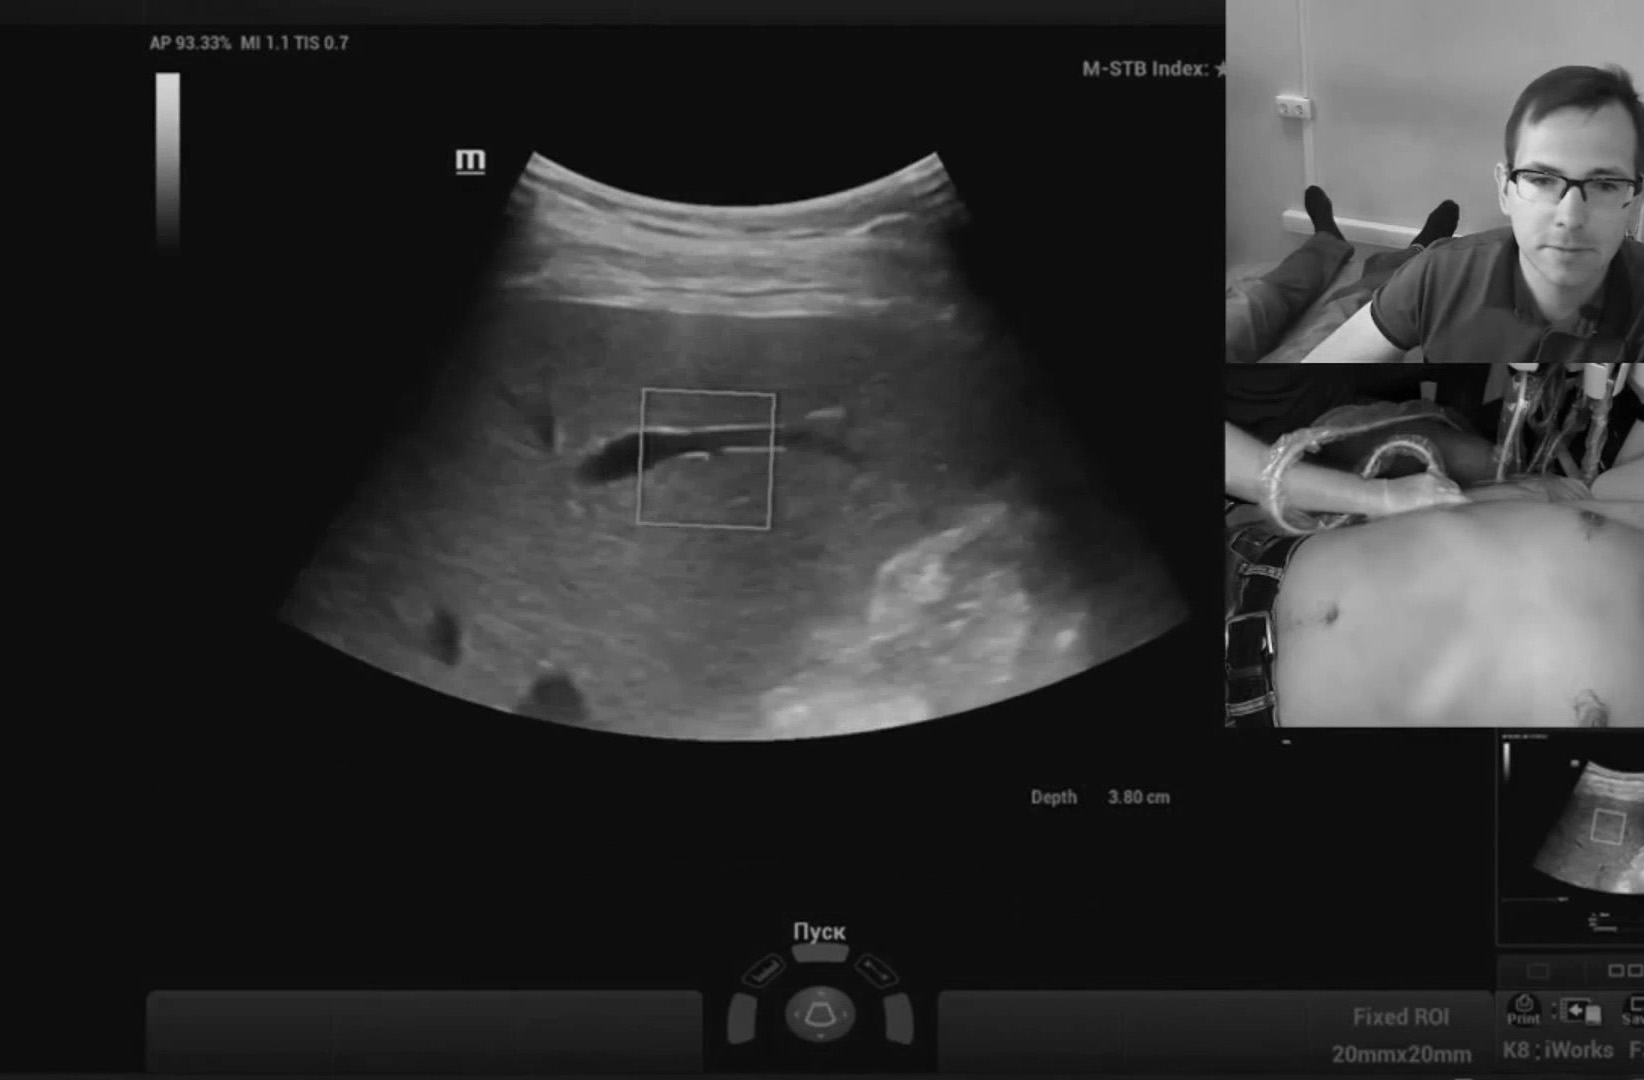

Обзор УЗИ: Отзыв о работе ультразвукового аппарата Mindray Resona 6

Работа с видео петлями реализована в полном объеме, то есть можно снять видео без оптимизации и отпустить пациента, оптимизацию провести уже на отснятых петлях в удобное время. Наличие эластографии сдвиговой волны периодически заставляет забыть, что я врач УЗД, бывают дни, когда делаешь одну эластографию печени. Очень популярная методика.

Список возможных расчетов огромен, можно настроить меню калькулятора под себя, какими пользуюсь. Разброс частот на фазированном датчике довольно большой, что позволяет смотреть как новорождённых, так и взрослых. По сонным артериям также без проблем, проникающая способность шикарная, чувствительность допплера шикарная, авто-настройка допплера - вплоть до угла сканирования. Анализ стабильности бляшек по системе GSM уже встроен, надо только вынести его в меню расчетов».